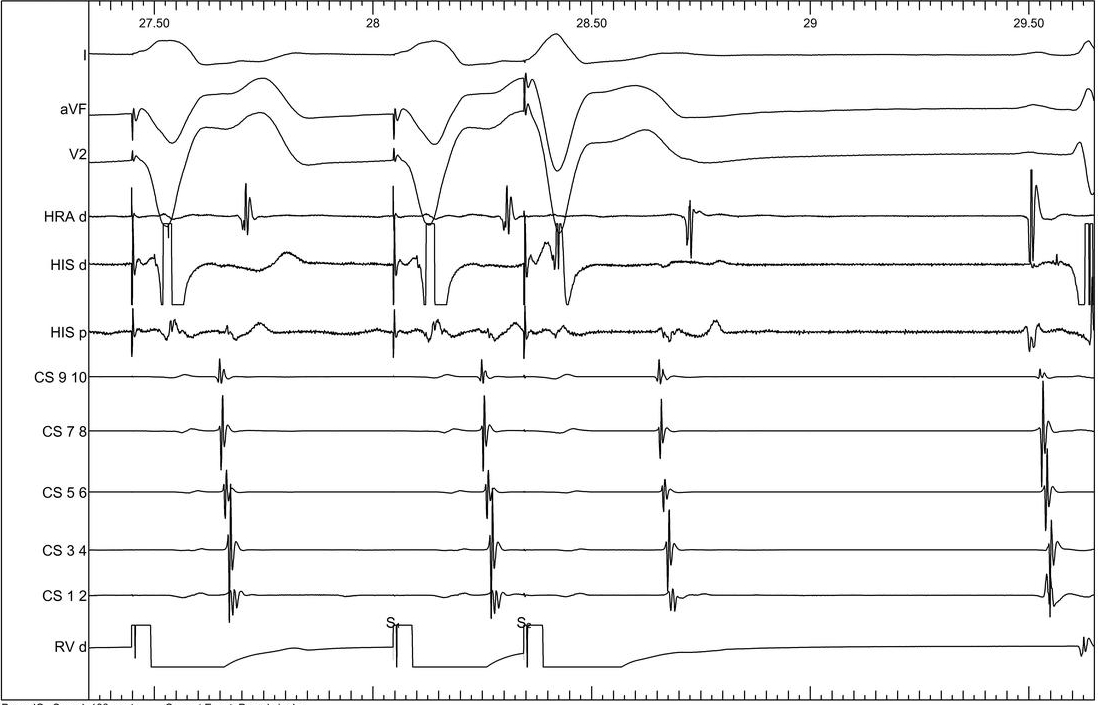

Incremental ventricular pacing

01_vawb.jpg